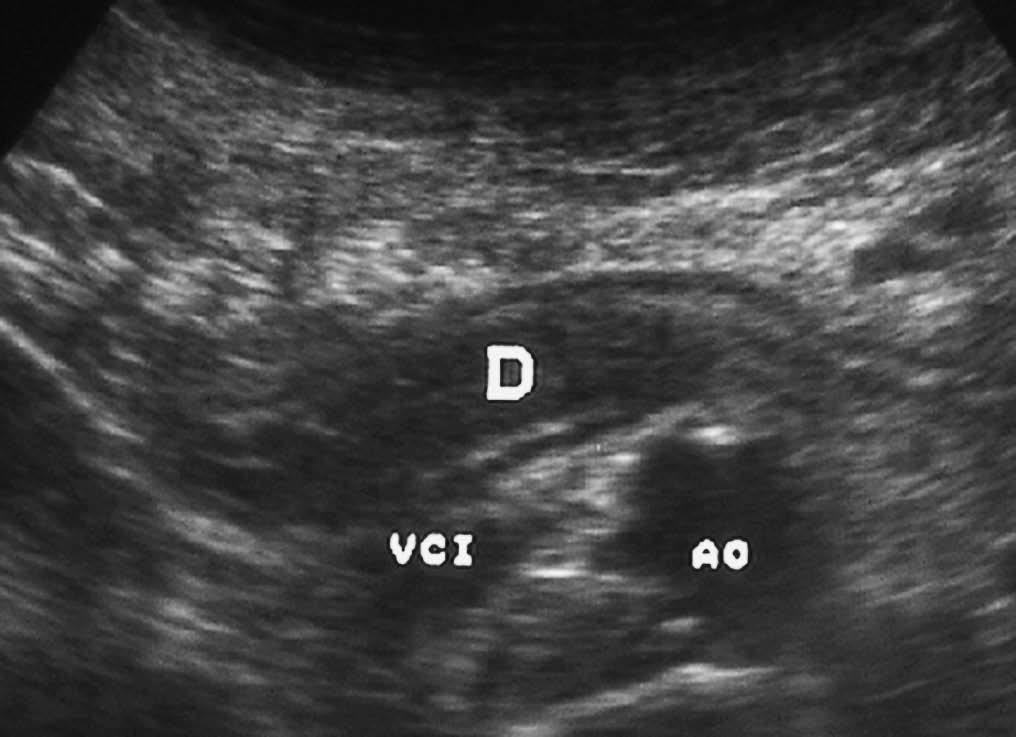

La enfermedad de Crohn afecta al duodeno de forma variable, apareciendo signos radiológicos en un 4% de los pacientes. Se manifiesta como un engrosamiento concéntrico y homogéneo de la pared, que puede producir estenosis de la luz intestinal (fig. 8). La existencia de actividad inflamatoria se identifica ecográficamente como aumento de la vascularización con modo doppler color. En la TC se observa la captación de la pared duodenal con afectación de la grasa adyacente.

Fig. 8--Enfermedad de Crohn duodenal. Corte ecográfico transversal donde se observa un engrosamiento concéntrico de la pared duodenal (D), que respeta la estructura de capas. VCI: Vena cava inferior; AO:aorta.